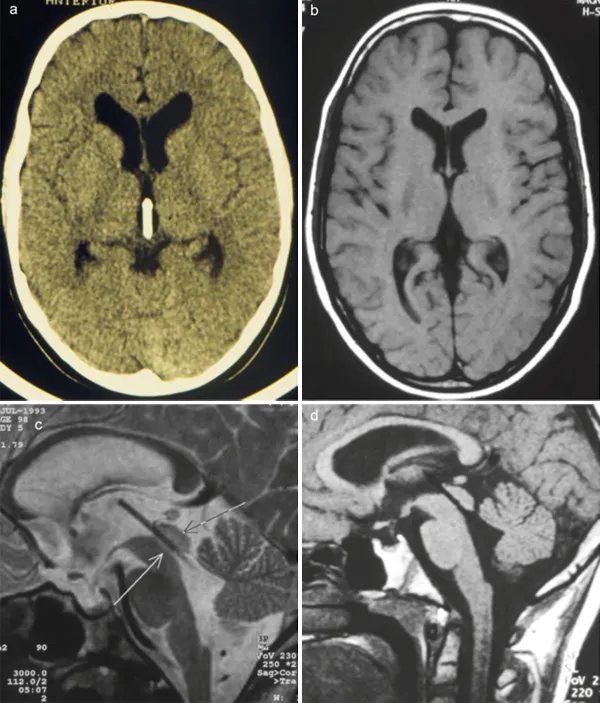

术后首日的计算机断层扫描及磁共振图像(图3)确认了经导水管支架已被精准放置于最佳位置。侧脑室与第三脑室的体积呈现明显回缩。

术后,男孩的临床症状获得完全缓解。

图3:术后CT(a)、磁共振图像(b、c、d)均显示导水管支架的定位情况。此外,侧脑室及第三脑室体积的明显减小,表明支架功能完好。